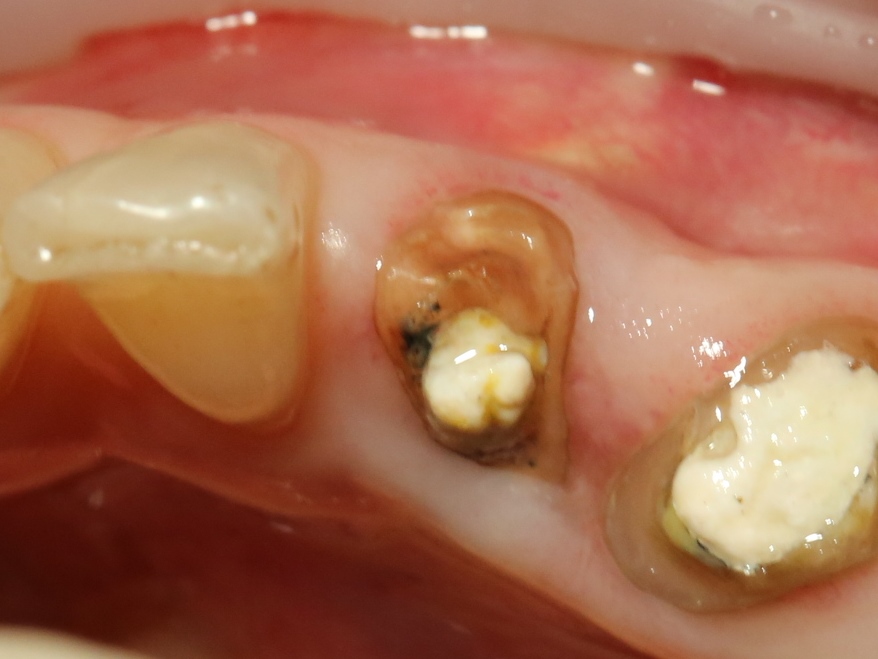

Немедленная имплантация — оптимальное решение в любой клинической ситуации